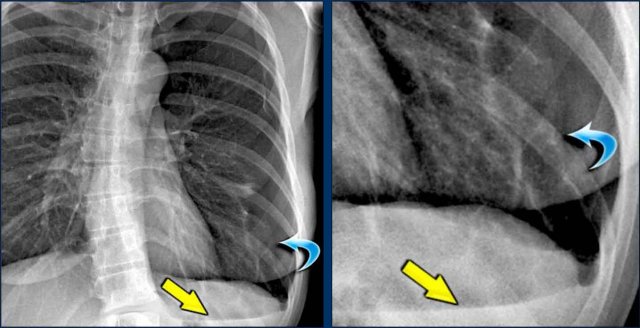

Hidden Areas (3): Pneumonia Below the Diaphragm

In this case, a pneumonia was primarily located below the right diaphragmatic dome (yellow arrow), within the posterior basal segment of the right lower lobe.

• On the lateral view, there is an increase in opacity over the lower thoracic vertebrae, indicating lower lobe consolidation (arrow).

• Again, image magnification may be necessary for adequate assessment.